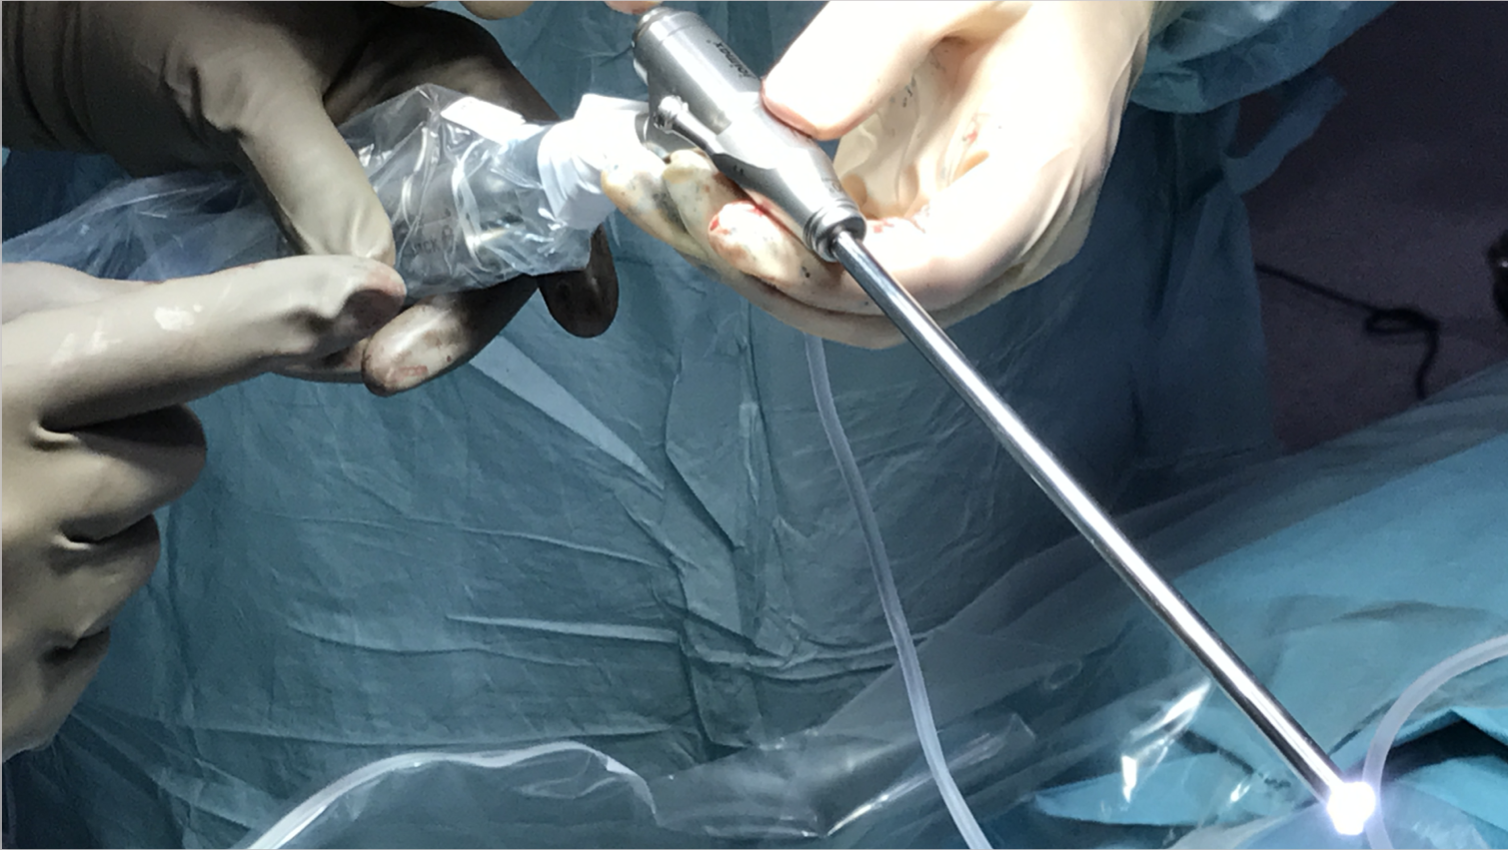

- Endoscopio: Intrumento con cámara integrada que permite realizar abordajes a las cavidades del cuerpo a través de incisiones milimétricas. La cirugía se visualiza en una pantalla.

Cirugía endoscópica de la columna lumbar

Una incisión de 1 centímetro

Se puede realizar la extracción de una hernia de disco a través de un endoscopio. Se realizar una incisión de 1 cm y se trabaja a través de un canal milimétrico. Así se minimiza el daño a la piel, músculo y hueso, reduciendo al mínimo el sangrado y las cicatrices.